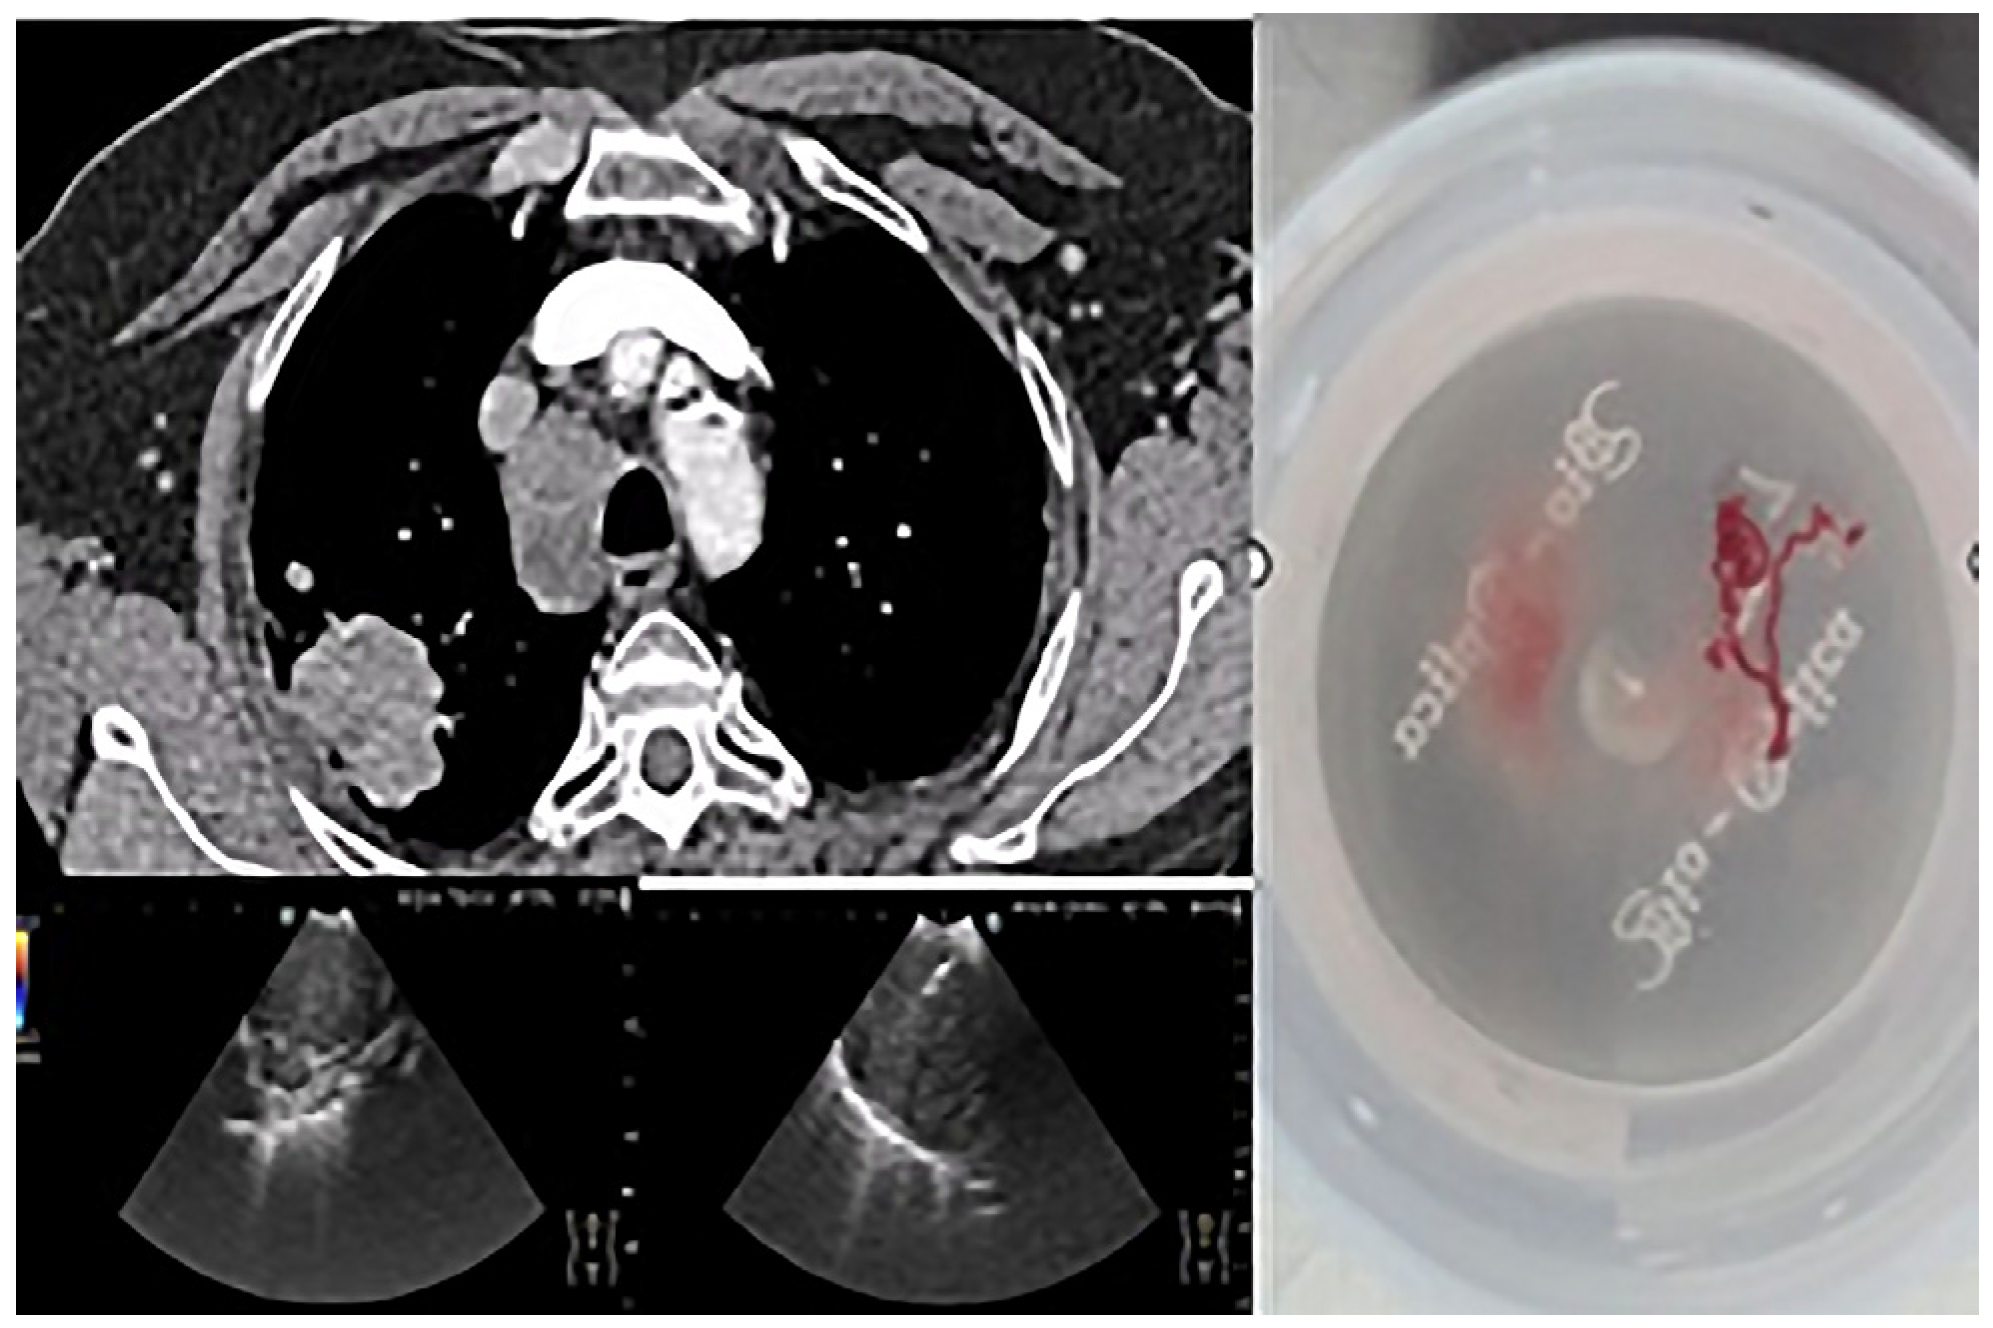

The importance of using EBUS-TBNA in this study is illustrated in Figure 1, which shows a lymph node puncture procedure in a patient with non-small cell carcinoma. In this example, the targeted lymph node station (4R) is annotated in the image. Sampling was performed using a 22G needle, and a scale bar has been added to provide spatial reference for the structures visualized. This technique allowed material suitable for complete characterization to be obtained without resorting to invasive surgical methods.

Figure 1. EBUS-TBNA in a 69-year-old ex-smoker male patient with no endobronchial tumor expression. Local anesthesia and mild sedation were used for transbronchial needle aspiration from 4R lymph node station, as shown in the thoracic CT section. Small cell carcinoma was confirmed and staged (N descriptor) in the same procedure. Immunohistochemical profile: TTF1-positive, SYN-positive, ki67-positive 98% in tumor cells.